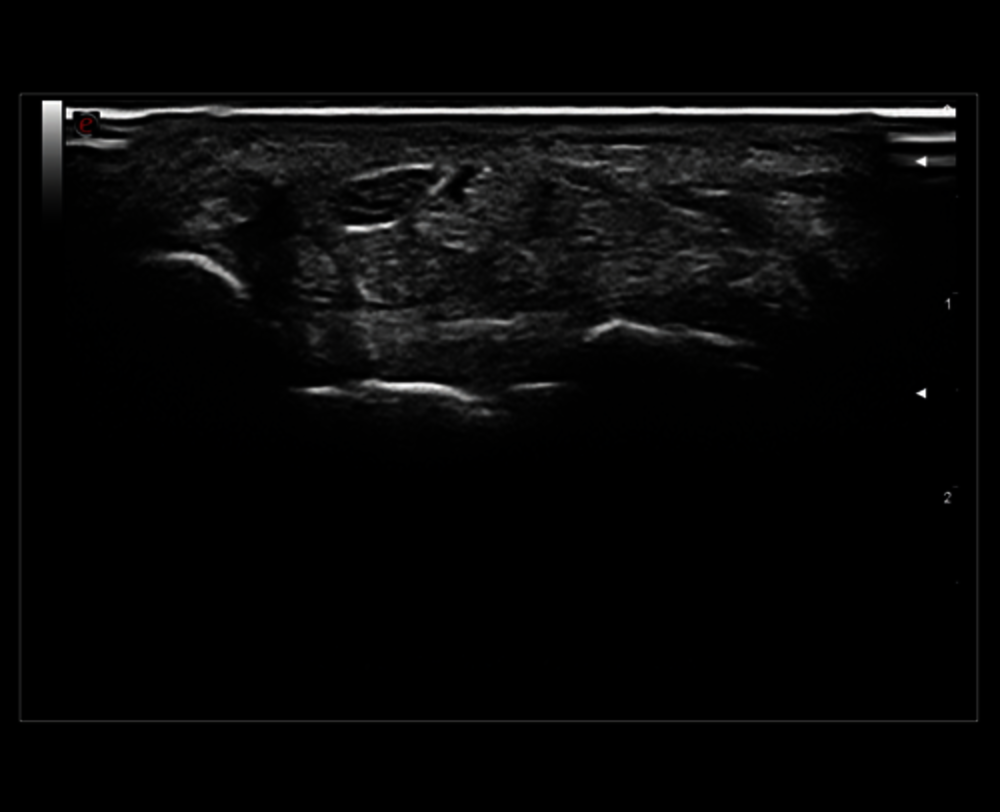

MSK zobrazení ramene

Vysoké rozlišení B-módu na středním nervu

Výkonový Doppler v oblasti zánětu akutní polyartritidy se sondou 18 MHz

Vyšetření spánkové tepny pomocí sondy s velmi vysokou frekvencí (22 MHz)